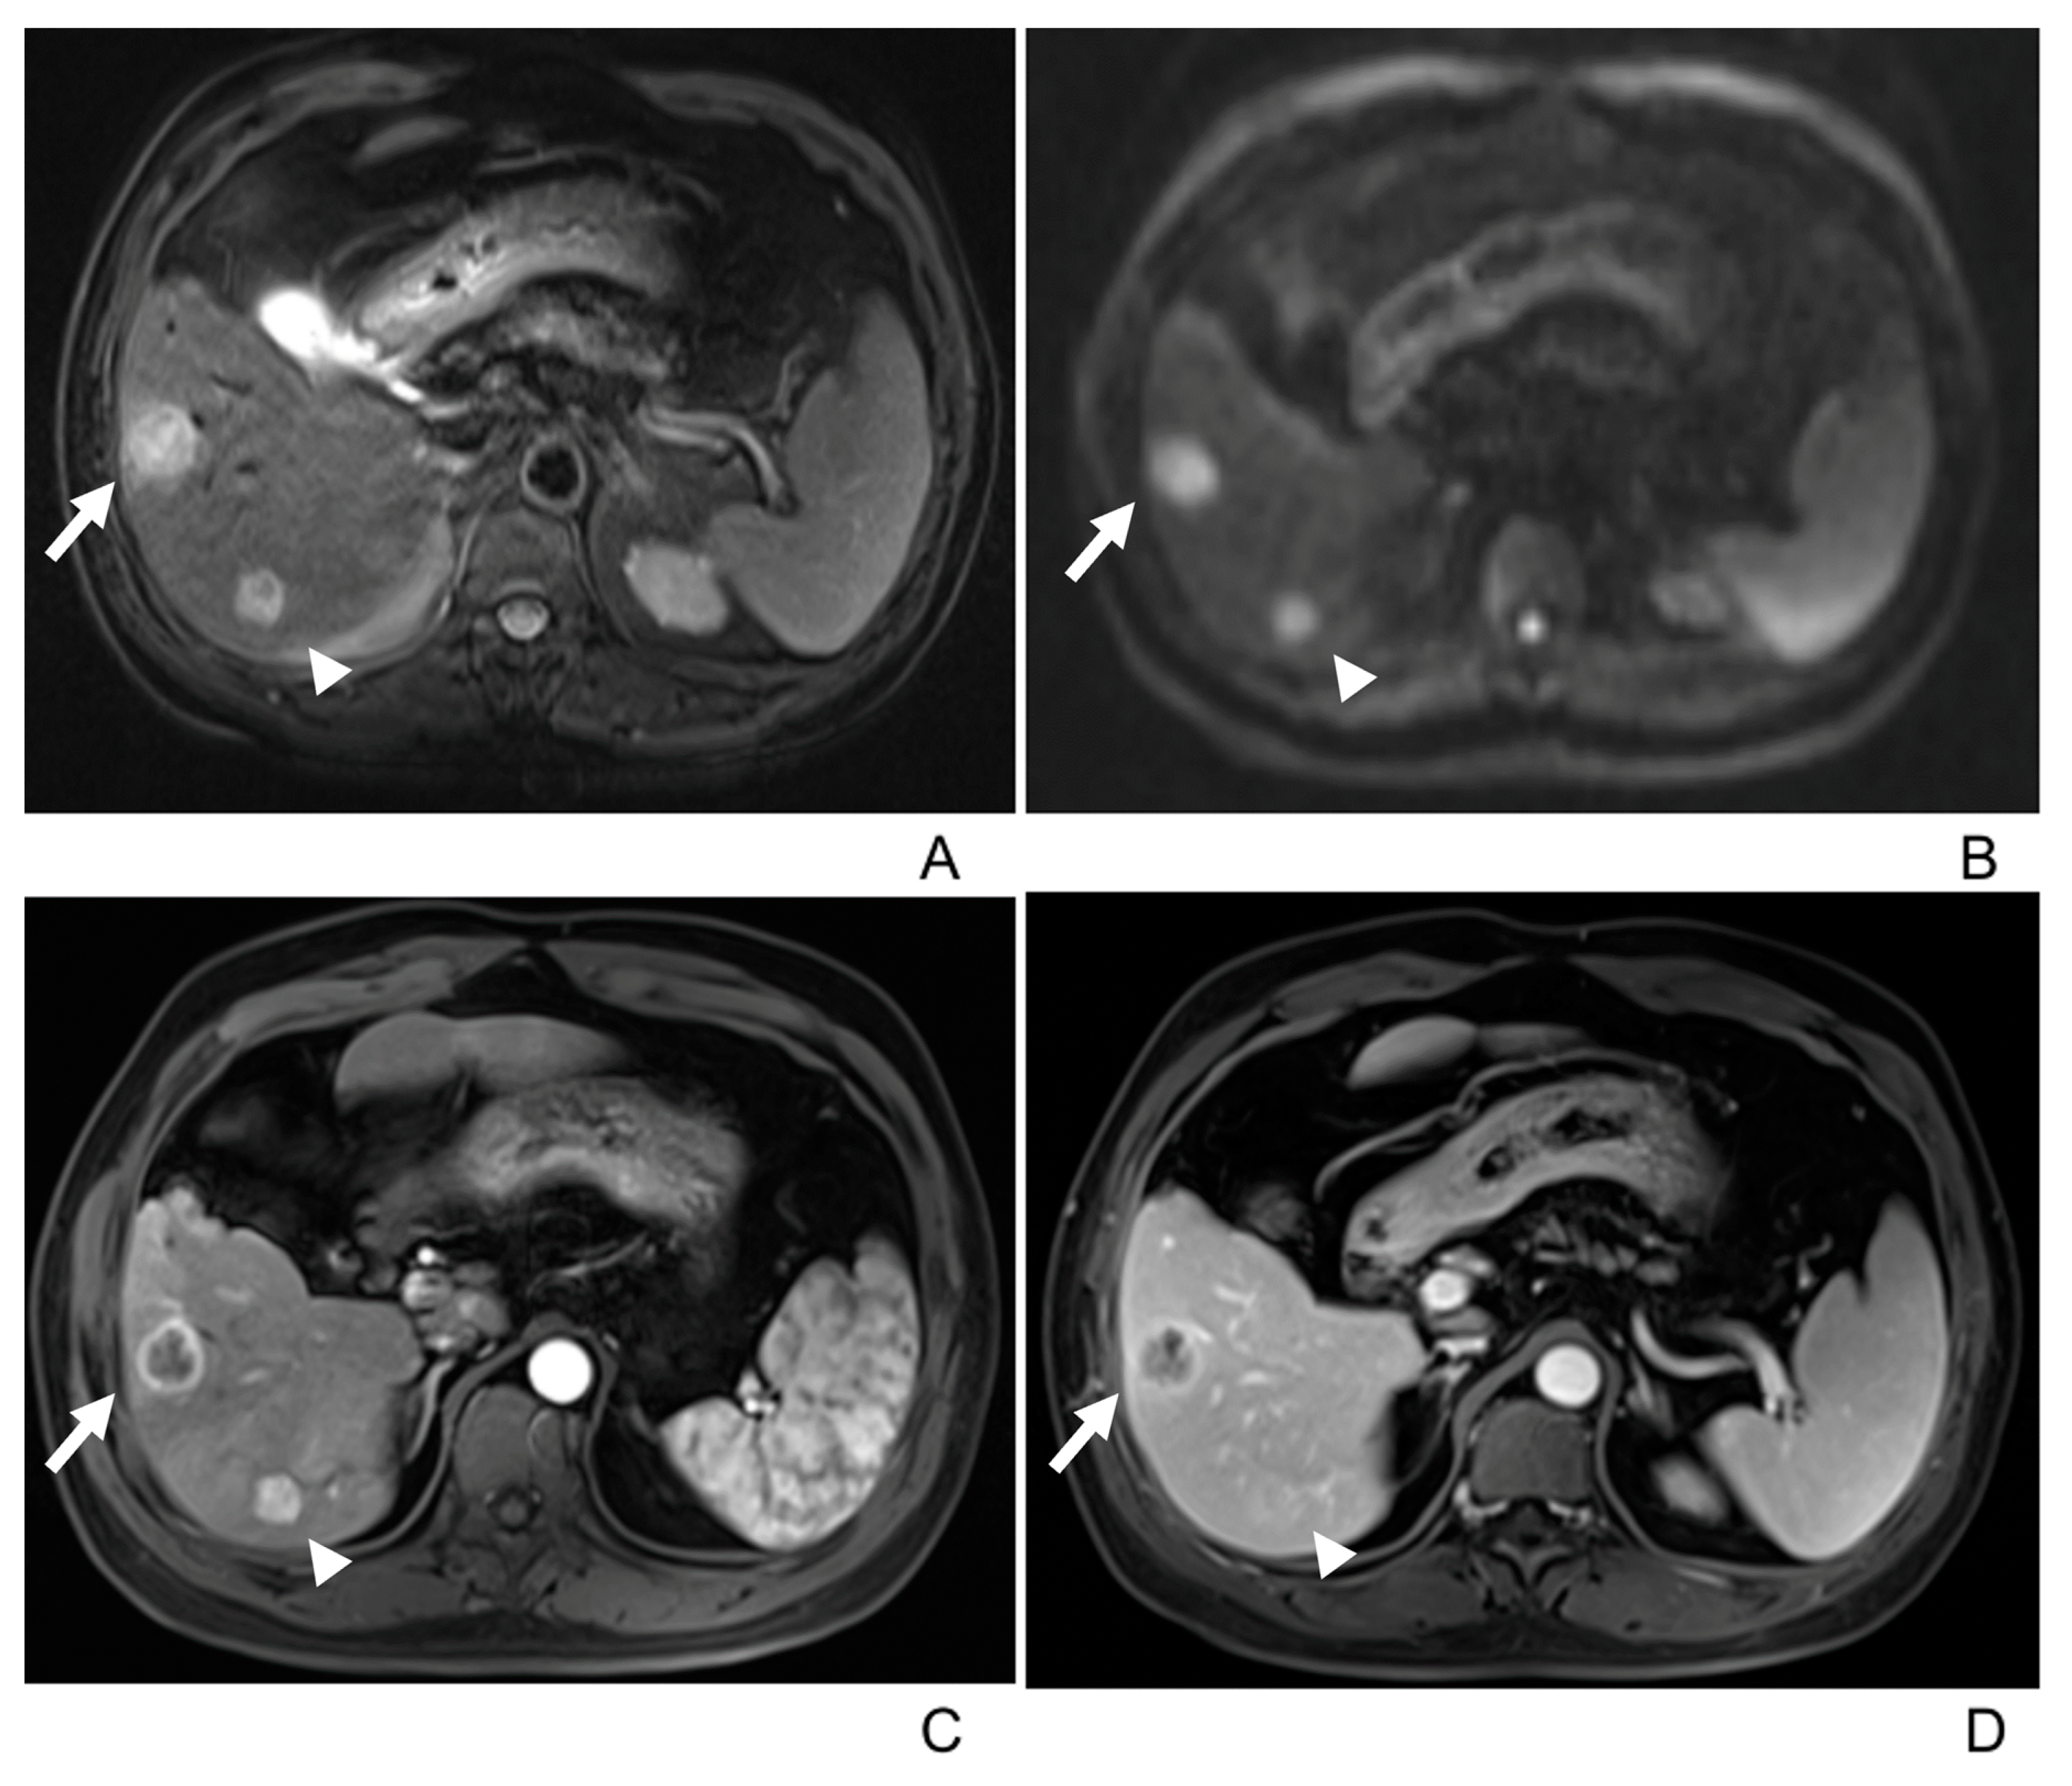

3.2. Imaging Manifestations

- Two tumors had associated satellite lesions.

- Four patients had portal vein tumor thrombosis (Figure 3).

- Three patients exhibited intrahepatic biliary dilation, and one patient had distal metastasis on the 12th rib (Figure 3).

| Dynamic enhancement patterns | |

| Type A a | 21(55%) |

| Type B b | 10(26%) |

| Type C c | 7(18%) |

| Capsular enhancement | 22/38(58%) |

| Type A/Type B/Type C | 13/9/0/(62%/90%/0) |

| Satellite lesion | 2/38(6%) |

| Venous tumor thrombus | 4/38(11%) |

| Biliary dilatation | 3/38(8%) |